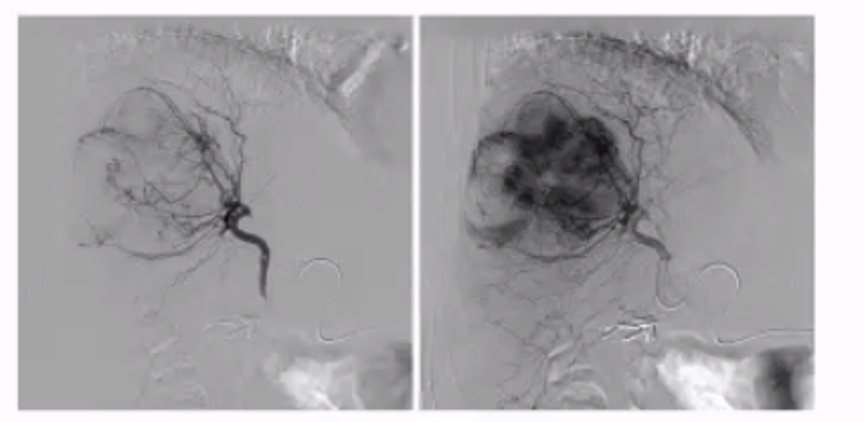

what is a potential complication of embolization of the selected vessel?

ovarian artery is selected in the right image.

Potential complication of ovarian failure

This is a pt with uterine fibroids with some blood supply coming from an enlarged ovarian artery